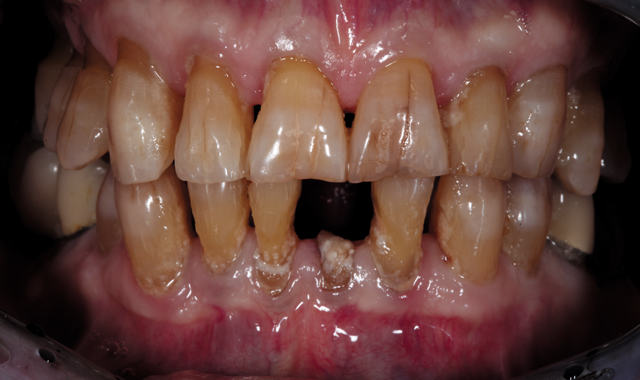

Fig. 1

An 88-year-old man presented for restoration of tooth #25, which was fractured and had been endodontically treated (Fig. 1). A thorough intraoral and radiographic examination was performed, which revealed damage to the remaining anterior mandibular teeth incurred over the years as a result of scaling and curettage (Fig. 2). This damage to the

Fig. 2

root surface of the lower incisors-which was visible on the radiograph (Fig. 3)-is known as “Riffle-ization.” Described by Dr. Riffle as a technique for removing every last bit of calculus during repeated root scaling, what is now known as “Riffle-izing," ultimately-over the years-changes the shape of the neck of the tooth to resemble an hour glass.

Therefore, based on the clinical and visual evaluation, the preferred treatment would be to restore the fractured #25 with a post and crown and four splinted crowns to restore the anatomy of the four incisors and increase their resistance to both mobility and fracture.